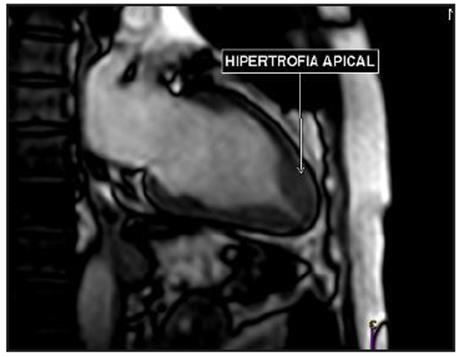

Estudio de RM de corazón (Figura 3), confirmó hipertrofia asimétrica del ápex, espesor parietal apical durante la diástole de 17 mm y relación del espesor parietal/pared posterior de 1.54, con dinámica segmentaria y función sistólica global conservada. No se detectaron gradientes obstructivos a nivel del ventrículo izquierdo.

El diagnóstico depende de la detección de hipertrofia apical localizada por medio de imagen y la ecocardiografía ha sido la primera línea para esto. Sin embargo, hay limitaciones para la correcta visualización del ápex y su hipertrofia, por lo que puede pasar inadvertida. Estas limitaciones son superadas a través de la RM de corazón, incluso en casos donde fueron omitidos por ecocardiografía 7. Los criterios diagnósticos por resonancia son: espesor de la pared apical mayor a 15 mm y/o una relación entre el espesor de la pared apical y basal del ventrículo izquierdo ≥ 1.3-1.5 8.